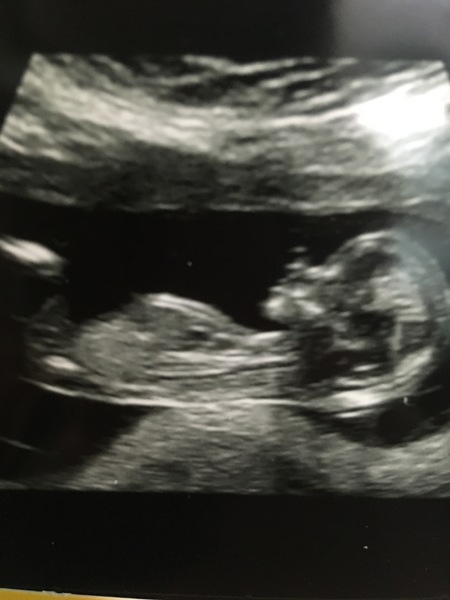

Had my scan today and confirmed I'm 11+1 so EDD is 27th June. A very wriggly baby!! Didn't stay still long enough to get a really good picture so she gave us them for free.